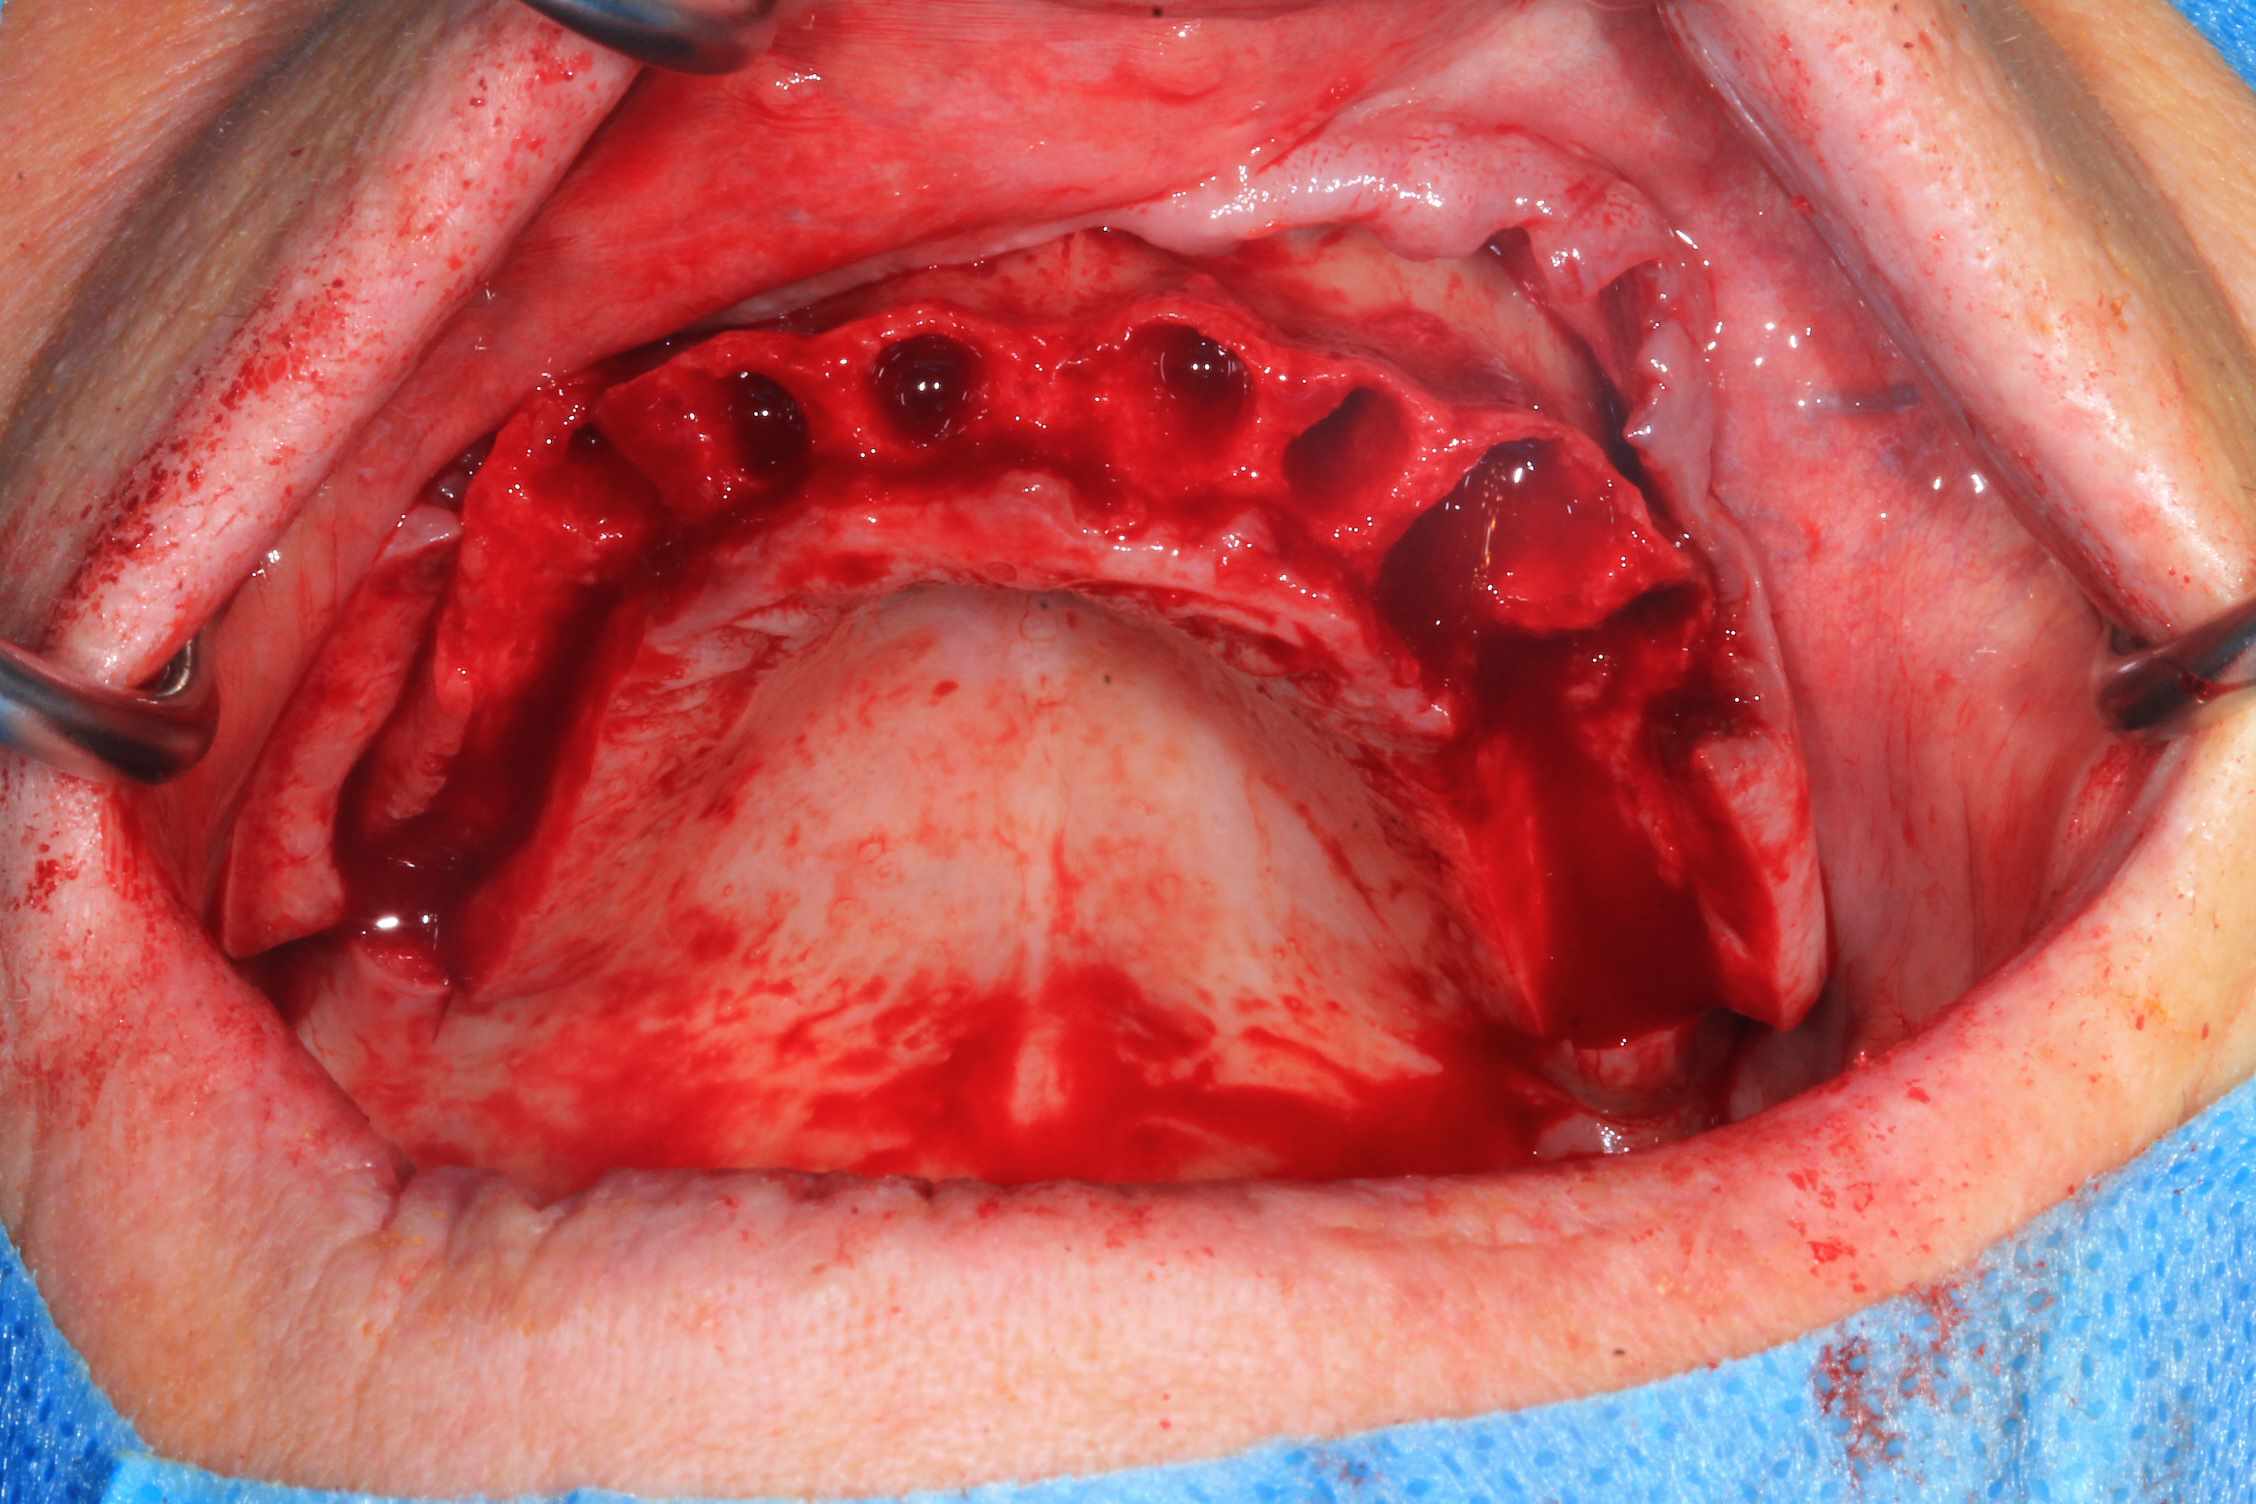

jeff

Cas 2 , suite : avec une saussage au passage..

le patient arrive a 9 h, Prise de sang, PRF, injection de corticoïde, anesthésie et installation au bloc. Premier coup de bistouri a 9h30. Dernière suture a 11h30.